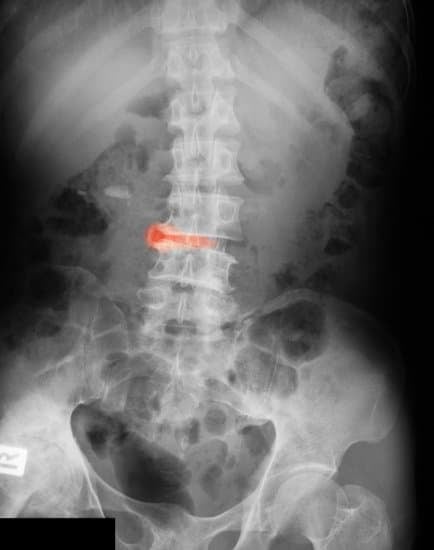

3. 강직성 척추염 진단 방법

📌 X-ray는 질병 진행이 된 후에 변화가 보일 수 있어, 조기 진단에는 MRI가 더욱 유용합니다.